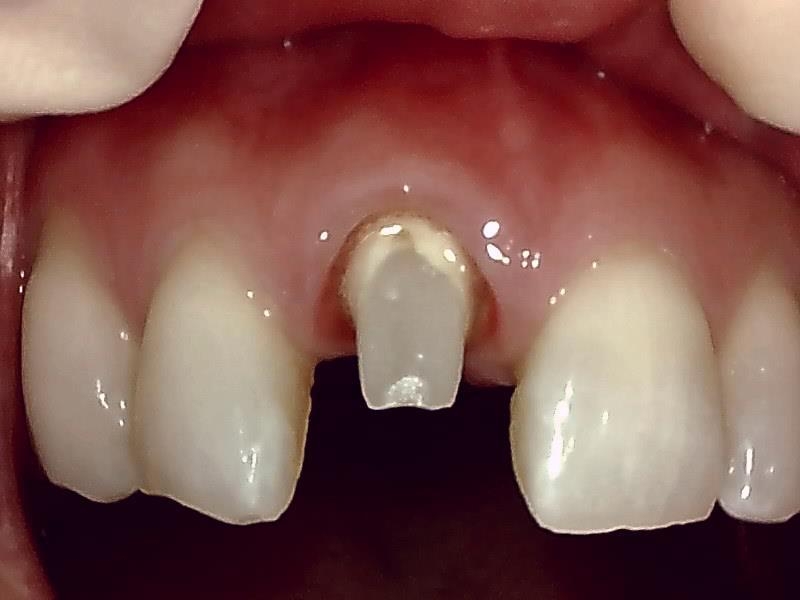

ジルコニアセラミック冠の装着前の支台歯形成(写真)

仮歯の装着して近心歯肉の回復を待つ。

仮歯の装着後、歯肉の治癒期間は後1~2週間後程度になる。